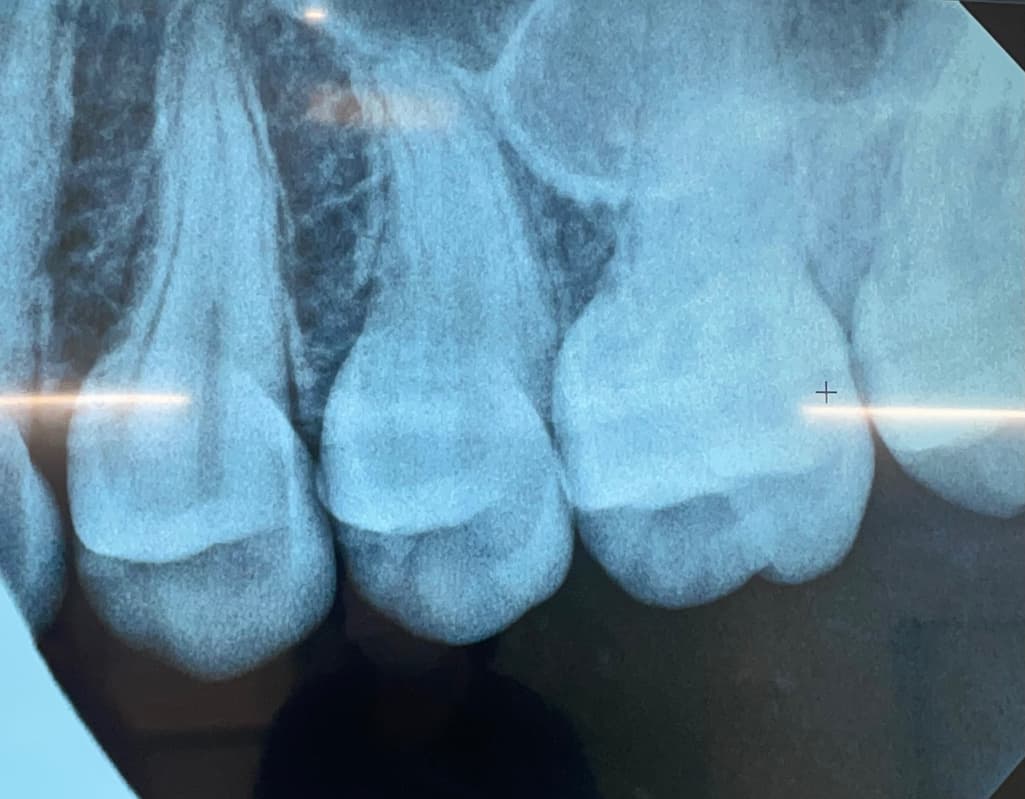

치아사이 충치 맞나요?

왼쪽에서 첫번째 두번째 사이에 충치가 발생해서 치료 필요하다 하셨는데 그럼 나머지 치아사이에는 충치 없는 거 맞나요?

치아 사이의 충치가 다른 치아에도 있지만 해당 부위의 충치가 더 커 보이며 사진만으로는 판별이 어렵습니다.

방사선 사진으로 봤을 경우 약간의 음영이 보이긴 합니다. 하지만 충치라고 단언할 순 없으며 육안으로 추가적인 확인이 필요할 것으로 생각됩니다.

엑스레이 상으로 치아 사이에 충치가 잇는것처럼 보입니다. 인레이 또는 레진을 하시면될것같습니다.